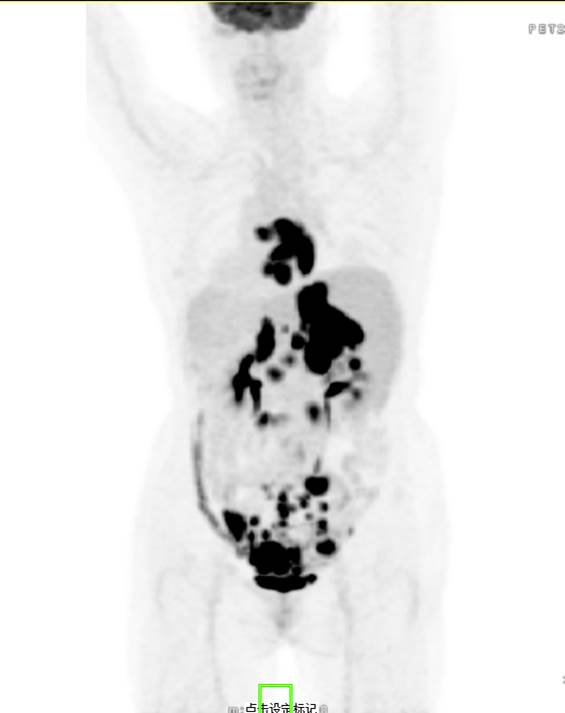

PET/CT影像圖